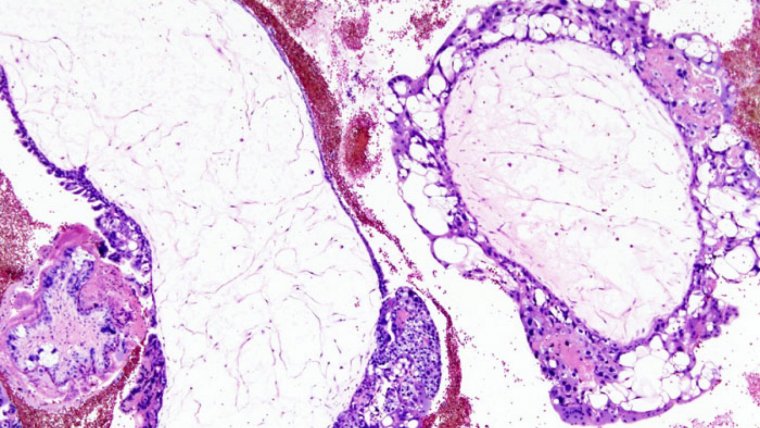

La mola hidatiforme, que como hemos dicho previamente también es llamada “embarazo molar”, es una alteración del embarazo caracterizada por el crecimiento anormal de los trofoblastos, que son las células a partir de las cuales se desarrolla la placenta en condiciones normales.

Existen dos tipos de mola hidatiforme: la completa y la parcial. Hablamos de embarazo molar completo cuando el tejido fetal no llega a desarrollarse en ningún grado y la placenta se encuentra inflamada, tiene un aspecto poco habitual y forma quistes llenos de líquido. En los casos de mola completa en ocasiones ni siquiera se forma la placenta.

Por contra, en la mola hidatiforme parcial es posible observar tejidos placentarios normales, si bien combinados con otros de naturaleza patológica. De hecho puede que incluso se forme parcialmente el feto, si bien éste no podrá sobrevivir a la gestación y lo más probable es que sea expulsado por el organismo de la madre por medio de un aborto espontáneo durante el primer trimestre del embarazo.